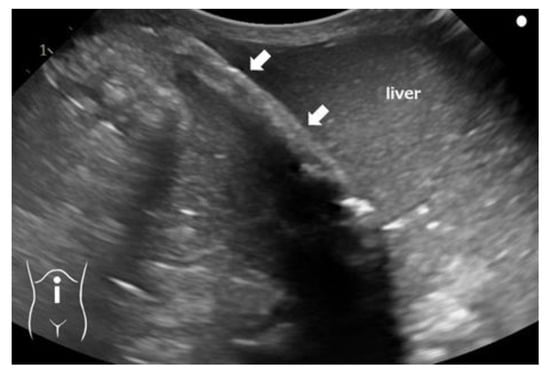

Umbilical Vein Calcification Associated with Double-Lumen Catheter Malpositioning in an Extremely Low-Birth-Weight Infant

2. Case Presentation